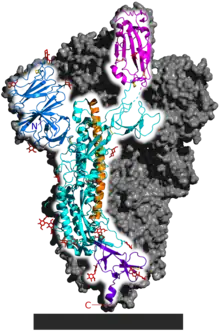

- "It's a very complicated receptor binding process compared to most virus spike proteins," Benton said. "Flu and HIV have a more simple activation process." The coronavirus is covered in spike proteins, and it's likely only a small fraction of them go through these conformational changes, bind to human cells and infect them, Benton said.

We know that the spike can adopt all these states that we were talking about," said co-lead author Antoni Wrobel, who is also a postdoctoral research fellow at the Francis Crick Institute's Structural Biology of Disease Processes Laboratory. "But whether each of the spikes adopts all of them we can't say because we can see only kind of snapshots."

The spike protein is very quick to change. In the lab, the spike can morph into all of these different conformations in less than 60 seconds, Wrobel told Live Science. But "this will be very different in a real infection; everything will be slower because the receptor will be stuck on the surface of a cell so you have to allow time for the virus to diffuse to this receptor," Benton said.

Why does the spike protein go through this many conformational changes to infect a cell? It "may be a way of the virus protecting itself from recognition by antibodies," Benton said. When the spike protein is in its closed states, it hides the site that binds with the receptor, maybe to avoid antibodies coming in and binding to that site instead, he said.- Donald Benton and Antoni Wrobel as quoted by Yasemin Saplakoglu in ”Coronavirus spike protein morphs into 10 different shapes to invade cells”, Live Science, (September 28, 2020)

Compared with HIV, SARS-CoV-2 is changing much more slowly as it spreads. But one mutation stood out to Korber. It was in the gene encoding the spike protein, which helps virus particles to penetrate cells. Korber saw the mutation appearing again and again in samples from people with COVID-19. At the 614th amino-acid position of the spike protein, the amino acid aspartate (D, in biochemical shorthand) was regularly being replaced by glycine (G) because of a copying fault that altered a single nucleotide in the virus’s 29,903-letter RNA code. Virologists were calling it the D614G mutation.

In April, Korber, Montefiori and others warned in a preprint posted to the bioRxiv server that “D614G is increasing in frequency at an alarming rate”1. It had rapidly become the dominant SARS-CoV-2 lineage in Europe and had then taken hold in the United States, Canada and Australia. D614G represented a “more transmissible form of SARS-CoV-2”, the paper declared, one that had emerged as a product of natural selection. - Viruses that encode their genome in RNA, such as SARS-CoV-2, HIV and influenza, tend to pick up mutations quickly as they are copied inside their hosts, because enzymes that copy RNA are prone to making errors. After the severe acute respiratory syndrome (SARS) virus began circulating in humans, for instance, it developed a kind of mutation called a deletion that might have slowed its spread.

But sequencing data suggest that coronaviruses change more slowly than most other RNA viruses, probably because of a ‘proofreading’ enzyme that corrects potentially fatal copying mistakes. A typical SARS-CoV-2 virus accumulates only two single-letter mutations per month in its genome — a rate of change about half that of influenza and one-quarter that of HIV, says Emma Hodcroft, a molecular epidemiologist at the University of Basel, Switzerland.

D614G’s rapid rise in Europe drew Korber’s attention. Before March — when much of the continent went into lockdown — both unmutated ‘D’ viruses and mutated ‘G’ viruses were present, with D viruses prevalent in most of the western European countries that geneticists sampled at the time. In March, G viruses rose in frequency across the continent, and by April they were dominant, reported Korber, Montefiori and their team. - The first team to report pseudovirus experiments on D614G, in June, was led by Hyeryun Choe and Michael Farzan, virologists at the Scripps Research Institute in La Jolla, California5. Several other teams have posted similar studies on bioRxiv (Montefiori’s experiments, and those of another collaborator, appeared in the Cell paper2). The teams used different pseudovirus systems and tested them on various kinds of cell, but the experiments pointed to the same conclusion: viruses carrying the G mutation infected cells much more ably than did D viruses — up to ten times more efficiently, in some cases.

In laboratory tests, “all of us agree that D to G is making the particles more infectious”, says Jeremy Luban, a virologist at the University of Massachusetts Medical School in Worcester. But these studies come with many caveats — and their relevance to human infections is unclear. “What’s irritating are people taking their results in very controlled settings, and saying this means something for the pandemic. That, we are so far away from knowing,” says Grubaugh. The pseudoviruses carry only the coronavirus spike protein, in most cases, and so the experiments measure only the ability of these particles to enter cells, not aspects of their effects inside cells, let alone on an organism. They also lack the other three mutations that almost all D614G viruses carry. “The bottom line is, they’re not the virus,” says Luban. - Some labs are now working with infectious SARS-CoV-2 viruses that differ by only the single amino acid. These are tested in laboratory cultures of human lung and airway cells, and in lab animals such as ferrets and hamsters. For labs with the experience and the biosafety capabilities to manipulate viruses, “this is like bread-and-butter kind of work”, says Sheahan. The first of those studies, led by researchers at the University of Texas Medical Branch in Galveston, was reported in a 2 September preprint6. It found that viruses with the mutation were more infectious than were D viruses in a human lung cell line and in airway tissues, and that mutated viruses were present at greater levels in the upper airways of infected hamsters6.

The origin of SARS-CoV-2 is still an open question (see ‘Family of killers’). The virus shares 96% of its genetic material with a virus found in a bat in a cave in Yunnan, China4 — a convincing argument that it came from bats, say researchers. But there’s a crucial difference. The spike proteins of coronaviruses have a unit called a receptor-binding domain, which is central to their success in entering human cells. The SARS-CoV-2 binding domain is particularly efficient, and it differs in important ways from that of the Yunnan bat virus, which seems not to infect people5.

But although genetic material from the virus is showing up in these various tissues, it is not yet clear whether the damage there is being done by the virus or by a cytokine storm, says Wendtner. “Autopsies are under way in our centre. More data will come soon,” he says. - SARS-CoV-2 is uniquely equipped for forcing entry into cells. Both SARS-CoV and SARS-CoV-2 bind with ACE2, but the receptor-binding domain of SARS-CoV-2 is a particularly snug fit. It is 10–20 times more likely to bind ACE2 than is SARS-CoV9. Wendtner says that SARS-CoV-2 is so good at infecting the upper respiratory tract that there might even be a second receptor that the virus could use to launch its attack.

- Scientists think that the involvement of furin could explain why SARS-CoV-2 is so good at jumping from cell to cell, person to person and possibly animal to human. Robert Garry, a virologist at Tulane University in New Orleans, Louisiana, estimates that it gives SARS-CoV-2 a 100–1,000 times greater chance than SARS-CoV of getting deep into the lungs. “When I saw SARS-CoV-2 had that cleavage site, I did not sleep very well that night,” he says.

The mystery is where the genetic instructions for this particular cleavage site came from. Although the virus probably gained them through recombination, this particular set-up has never been found in any other coronavirus in any species. Pinning down its origin might be the last piece in the puzzle that will determine which animal was the stepping stone that allowed the virus to reach humans. - Some researchers hope that the virus will weaken over time through a series of mutations that adapt it to persist in humans. By this logic, it would become less deadly and have more chances to spread. But researchers have not yet found any sign of such weakening, probably because of the virus’s efficient genetic repair mechanism. “The genome of COVID-19 virus is very stable, and I don’t see any change of pathogenicity that is caused by virus mutation,” says Guo Deyin, who researches coronaviruses at Sun Yat-sen University in Guangzhou.